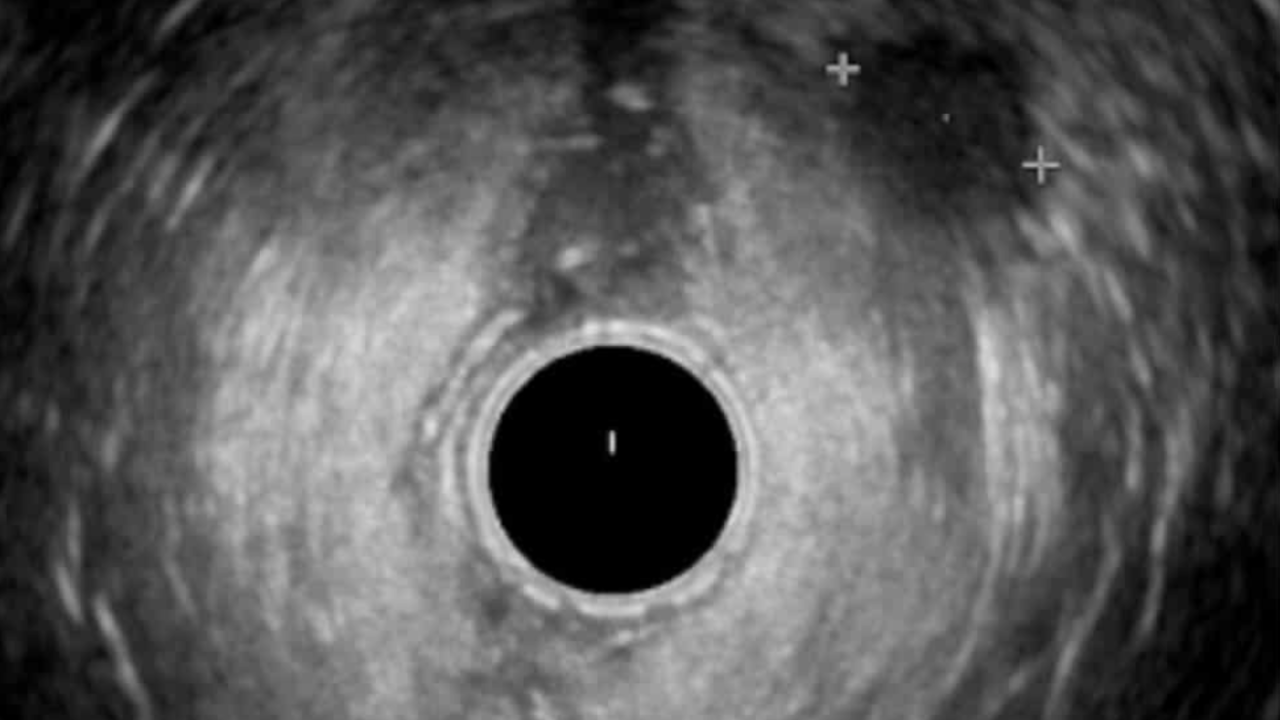

This 10-session live online mentorship programme will take you through a tried and tested fellowship where we will discuss indications, technique, interpretation and limitations of pelvic floor diagnostics, including; 1. Endoanal Ultrasound 2. Fluoroscopic Defecating Proctogram  3. MRI Defecating Proctogram 4. Anorectal Manometry The sessions will be designed to work with your busy schedule in mind and can be used weekly over a 12 week period or monthly over a 12 month period depending on the users learning needs and availability. Each session will comprise of teaching cases with short lectures exploring the visualised pathology and you can expect to see 100+ cases. A formative diagnostic imaging assessment will allow you to gain a certificate of completion, with a defined scope of practice, which you can be used to apply for your own departmental competency sign off.  You will also be asked to share anonymised examples of your own cases with your report to ensure your practice is at a high quality standard. The Ultrasound component of the material has been endorsed by the British Medical ultrasound Society and the additional modalities will be awarded credits in line with the Royal College of Radiologists accreditation scheme. This fellowship covers the essentials for any healthcare practitioner working with patients suffering with pelvic floor symptoms and aims to standardise your learning and give you access to global key opinion leaders from the comfort of your clinic. Please note spaces are limited so please enquire promptly to avoid disappointment. We look forward to hearing from you!

You will gain access to the Pelvic floor imaging Course, Community and Three one-on-one mentorship sessions with a Consultant Radiologist. ๐Ÿฉบ Master Pelvic Floor Imaging in 6 Weeks ๐Ÿฉบ  This course is suitable for healthcare professionals looking to increase knowledge of Pelvic floor imaging including: - Endoanal Ultrasound (EAUS) - Anorectal Manometry - Fluoroscopic Defecography - MRI Defecography What you'll get: You will gain INSTANT access to the community with weekly uploaded cases! Understand the indications and technique of performing these investigations Become proficient in Normal anatomy  Gain a comprehensive interpretation technique Explore a range of pathological cases  Gain an understanding of how to interpret Fluoroscopic and MRI Defecography  A Consultant-Led Online Course for Pelvic Floor Healthcare professionals โœ… Course Overview: ๐Ÿ” Week 1 & 2 : On-Demand Module with Live webinar โ€” Endoanal Ultrasound  ๐Ÿ”  Week 3: On-Demand Module with Live webinar  - Anorectal Manometry ๐Ÿ”  Week 4: On-Demand Module with Live webinar  - Fluoroscopic DPG ๐Ÿ”  Week 5: On-Demand Module with Live webinar  - MRI Defecating proctogram ๐Ÿง  Week 6: On-Demand Module with Live webinar  - Consolidate a Multimodality Approach to Pelvic Floor Imaging - Final Quiz + with Live interpretation Session Join weekly live sessions covering real clinical cases using: Endoanal Ultrasound (EAUS) Anorectal Manometry Fluoroscopic DPG MRI Proctogram Each session includes guided interpretation, Q&A with consultant radiologists, and key takeaways you can apply immediately. Test your skills and reinforce your learning with a structured quiz followed by a live image interpretation discussion. ๐Ÿ’ก What Youโ€™ll Gain ๐Ÿ’ก  Confidence in reading pelvic floor imaging Hands-on learning with real cases Direct mentorship from expert consultant radiologists Access to the pelvic Floor Academy Community CPD/CME accreditation ๐Ÿ–ฅ๏ธ Course Format: 100% Online โ€“ Join from anywhere Live sessions + On-Demand Access Recordings available after each session Interactive community inside Kajabi ๐Ÿ“…  Course Start Date: 07th March 2026 Spots are limited to ensure an interactive learning experience. You will gain INSTANT access to the community with weekly uploaded cases! This course is intended to give the theoretical knowledge necessary to understand pelvic floor imaging and acts as a theoretical aid your clinical practice. CPD Accredited This community is a place to: ๐Ÿ”น Share knowledge and learn together ๐Ÿ”น Analyse real-world cases and imaging scenarios ๐Ÿ”น Stay up to date with the latest techniques and guidelines ๐Ÿ”น Collaborate and connect with peers across multiple disciplines We have helped over 500+ healthcare professionals across the UK, Europe and Middle east working in; Radiology, Obstetrics and Gynaecology, Uro-gynaecology, Colorectal surgery, Gastroenterology and Physiotherapy gain a higher level of understanding of the technique and interpretation of pelvic floor investigations.   What you will get access to: ๐Ÿ”น Weekly Case uploads with expert interpretation ๐Ÿ”น Expert moderators will comment on your uploaded cases ๐Ÿ”น Monthly detailed videos of real-world cases ๐Ÿ”น Monthly Live webinars covering imaging interpretation ๐Ÿ”น Webinars will be recorded for on-demand access ๐Ÿ”น Access to a growing Case library of pelvic floor imaging cases   Each week, weโ€™ll be posting a new case for you to review and interpret, alongside monthly video explainers to aid your understanding. We encourage you to ask questions, contribute your insights, and grow alongside your colleagues. If this looks like the right place for you then we can't wait to meet you!

๐Ÿฉบ Master Pelvic Floor Imaging in 6 Weeks ๐Ÿฉบ  This course is suitable for healthcare professionals looking to increase knowledge of Pelvic floor imaging including: - Endoanal Ultrasound (EAUS) - Anorectal Manometry - Fluoroscopic Defecography - MRI Defecography What you'll get: You will gain INSTANT access to the community with weekly uploaded cases! Understand the indications and technique of performing these investigations Become proficient in Normal anatomy  Gain a comprehensive interpretation technique Explore a range of pathological cases  Gain an understanding of how to interpret Fluoroscopic and MRI Defecography  A Consultant-Led Online Course for Pelvic Floor Healthcare professionals โœ… Course Overview: ๐Ÿ” Week 1 & 2 : On-Demand Module with Live webinar โ€” Endoanal Ultrasound  ๐Ÿ”  Week 3: On-Demand Module with Live webinar  - Anorectal Manometry ๐Ÿ”  Week 4: On-Demand Module with Live webinar  - Fluoroscopic DPG ๐Ÿ”  Week 5: On-Demand Module with Live webinar  - MRI Defecating proctogram ๐Ÿง  Week 6: On-Demand Module with Live webinar  - Consolidate a Multimodality Approach to Pelvic Floor Imaging - Final Quiz + with Live interpretation Session Join weekly live sessions covering real clinical cases using: Endoanal Ultrasound (EAUS) Anorectal Manometry Fluoroscopic DPG MRI Proctogram Each session includes guided interpretation, Q&A with consultant radiologists, and key takeaways you can apply immediately. Test your skills and reinforce your learning with a structured quiz followed by a live image interpretation discussion. ๐Ÿ’ก What Youโ€™ll Gain ๐Ÿ’ก  Confidence in reading pelvic floor imaging Hands-on learning with real cases Direct mentorship from expert consultant radiologists Access to the pelvic Floor Academy Community CPD/CME accreditation ๐Ÿ–ฅ๏ธ Course Format: 100% Online โ€“ Join from anywhere Live sessions + On-Demand Access Recordings available after each session Interactive community inside Kajabi ๐Ÿ“…  Course Start Date: 07th March 2026 Spots are limited to ensure an interactive learning experience. You will gain INSTANT access to the community with weekly uploaded cases! This course is intended to give the theoretical knowledge necessary to understand pelvic floor imaging and acts as a theoretical aid your clinical practice. CPD Accredited